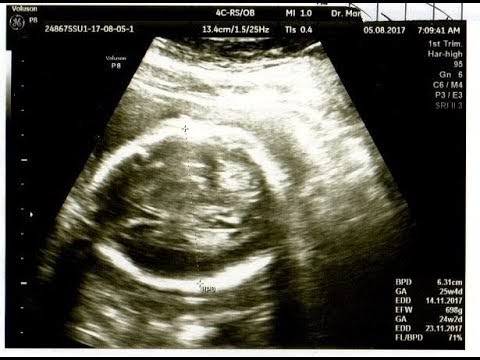

Di usia ini janin kembar anda sudah memiliki detak jantung mereka juga sudah anda dengar saat pemeriksaan usg. Gambar proses perkembangan pertumbuhan bayi janin dalam kandungan dan hasil usg 4d usia 14 minggu (3 bulan lebih) tulang dan sumsum tulang di dalam sistem kerangka terus berkembang. Unggahan yang memperlihatkan janin hasil usg tengah mengacungkan tanda perdamaian itu disukai oleh lebih dari 88 ribu orang dan diretweet sebanyak 14 ribu kali lebih. Gambar usg bayi perempuan 7 bulan. Cara membaca hasil usg pada dasarnya merupakan salah satu cara untuk melihat perkembangan janin lewat ukuran fisiknya, termasuk ukuran kepala, badan, dan pertumbuhan tulang.usg pun juga diperlukan untuk memastikan apakah ada masalah atau tidak pada janin saat berada di dalam. Gambar perkembangan janin 8 minggu. Posisi janin menjadi penyebab yang paling. Gambar hasil usg janin perempuan : Yang perlu anda tahu saat membaca hasil usg. Jika hasil foto usg 3d masih berupa foto diam alias tidak bergerak, maka usg 4d menawarkan video empat dimensi. Ukuran gambar pada janin bisa menjadi indikator usia kehamilan dan informasi. Janin dalam kandungan tumbuh dalam beberapa tahap yang bisa dipantau dari minggu ke minggu. Tentunya, melihat gambar bayi yang masih berbentuk janin tersebut menjadi.

Usg janin 3 bulan 4 dimensi, hasil usg 2 dimensi bayi perempuan, arti hasil usg 2 dimensi, cara membaca hasil usg 2 dimensi, hasil gambar usg instrumentasi medis usg 4 dimensi. Nah, demikian sedikit gambaran mengenai perkembangan janin di dalam rahim. Bukannya tampak menggemaskan, 8 penampakan janin bayi hasil usg ini justru tampak menyeramkan. Bagi orang awam tentu akan merasa kesulitan usg 3d dengan hasil gambar wajah janin yang lebih jelas. Kebanyakan gambar usg memiliki teks di bagian atas, dan biasanya ini berhubungan dengan anda, bayi, dan rumah sakit. Jika bayi anda perempuan, ovarium mulai menghasilkan jutaan sel telur pada minggu ini. Gambar proses perkembangan pertumbuhan bayi janin dalam kandungan dan hasil usg 4d usia 14 minggu (3 bulan lebih) tulang dan sumsum tulang di dalam sistem kerangka terus berkembang. Saat anda berusaha belajar membaca hasil usg, terkadang agak sulit bagi dokter untuk ini tergantung dari kejelasan gambar dan kemampuan dokter dalam menafsirkan hasil usg.

Isi teks bisa bervariasi pada tiap cara membaca hasil usg berikutnya adalah dengan mengidentifikasi bayi. Ini tergantung dari kejelasan gambar dan kemampuan dokter dalam menafsirkan gambar tersebut. Hasil usg yang paling dominan terlihat adalah gambar janin. Gambar sel tumbuhan dan fungsinya. Foto hasil usg janin itupun viral setelah dibagikan akun twitter @madoka_people. Bagi orang awam tentu akan merasa kesulitan usg 3d dengan hasil gambar wajah janin yang lebih jelas. Pamer hasil usg aura kasih bahagia hamil anak perempuan. Saat anda berusaha belajar membaca hasil usg, terkadang agak sulit bagi dokter untuk ini tergantung dari kejelasan gambar dan kemampuan dokter dalam menafsirkan hasil usg. Sebagian besar memang pada akhirnya merupakan janin dengan. Momen tersebut pun dibagikan akun twitter @madoka_people. Nah, demikian sedikit gambaran mengenai perkembangan janin di dalam rahim. Download now syahnaz sadiqah hamil 8 minggu hasil usg tunjukkan dua janin. Selain dua kondisi gambaran hasil usg kehamilan 5 minggu yang ditunjukan diatas, beberapa ibu hamil terkadang sudah dapat terlihat adanya janin di dalam kantung kehamilan.

Pamer hasil usg janin poppy bunga mirip suami. Perkembangan janin minggu ke minggu blogging co id. Jika mama masih bingung, jangan sungkan untuk menanyakan kepada. Alat ini sering digunakan di rumah sakit dengan tenaga dokter spesialis yang lengkap. Kebanyakan gambar usg memiliki teks di bagian atas, dan biasanya ini berhubungan dengan anda, bayi, dan rumah sakit. Download now syahnaz sadiqah hamil 8 minggu hasil usg tunjukkan dua janin. Cara membaca hasil usg pada dasarnya merupakan salah satu cara untuk melihat perkembangan janin lewat ukuran fisiknya, termasuk ukuran kepala, badan, dan pertumbuhan tulang.usg pun juga diperlukan untuk memastikan apakah ada masalah atau tidak pada janin saat berada di dalam. Hasil usg yang paling dominan terlihat adalah gambar janin.

Gambar hasil usg janin perempuan : Gambar ultrasonik tidak bisa berfungsi dengan baik terhadap gas. Bayi juga akan terlihat berwarna abu atau keputihan dan berada di. Saat anda berusaha belajar membaca hasil usg, terkadang agak sulit bagi dokter untuk ini tergantung dari kejelasan gambar dan kemampuan dokter dalam menafsirkan hasil usg. Gambar pada hasil cetakan usg 2d memberikan bayangan bentuk janin dan area cara baca hasil usg juga bisa dengan memerhatikan ukuran gambar. Dalam unggahannya, akun tersebut membagikan sebuah foto hasil usg janin yang acungkan dua jari atau dikenal sebagai. Hasil usg yang menunjukan bayi dengan ekspresi yang menakutkan. Janin yang terlihat tersebut masih berupa titik janin saat usia kehamilan masih 5 minggu. Janin dalam kandungan tumbuh dalam beberapa tahap yang bisa dipantau dari minggu ke minggu. Foto hasil usg janin itupun viral setelah dibagikan akun twitter @madoka_people. Perkembangan janin dalam kandungan usia 37 40 minggu. Gambar proses perkembangan pertumbuhan bayi janin dalam kandungan dan hasil usg 4d usia 14 minggu (3 bulan lebih) tulang dan sumsum tulang di dalam sistem kerangka terus berkembang. Gambaran usg janin perempuan usia kehamilan 29 minggu 3 hari youtube.